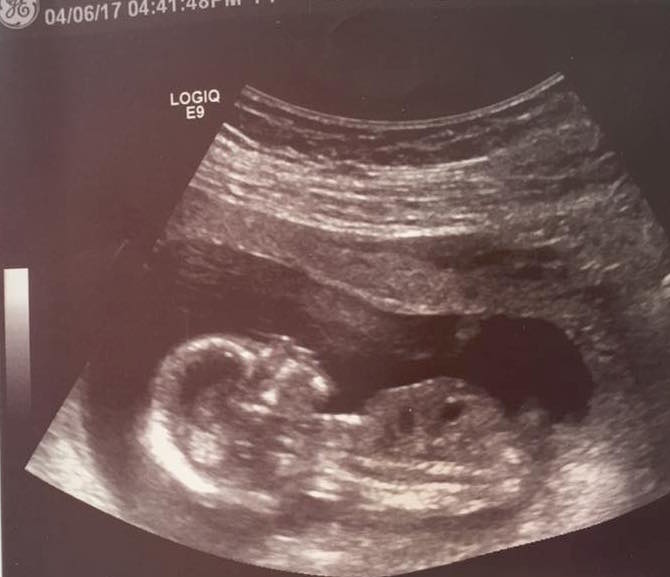

Skull Theory 14+2 weeks

SO, this is baby #4, and I'm not finding out the gender until birth. But I LOVE looking at photos for ramzi/nub/skull theory so I thought I would just post this one and see what the guesses were. =)

14 weeks and 2 days.

The skull looks super girlie but it's not as reliable!

I'm due just 3 days after you! (Oct 3.) I have 3 boys, and comparing skull photos to theirs, this one is definitely showing girly. But I don't want to get my hopes up!